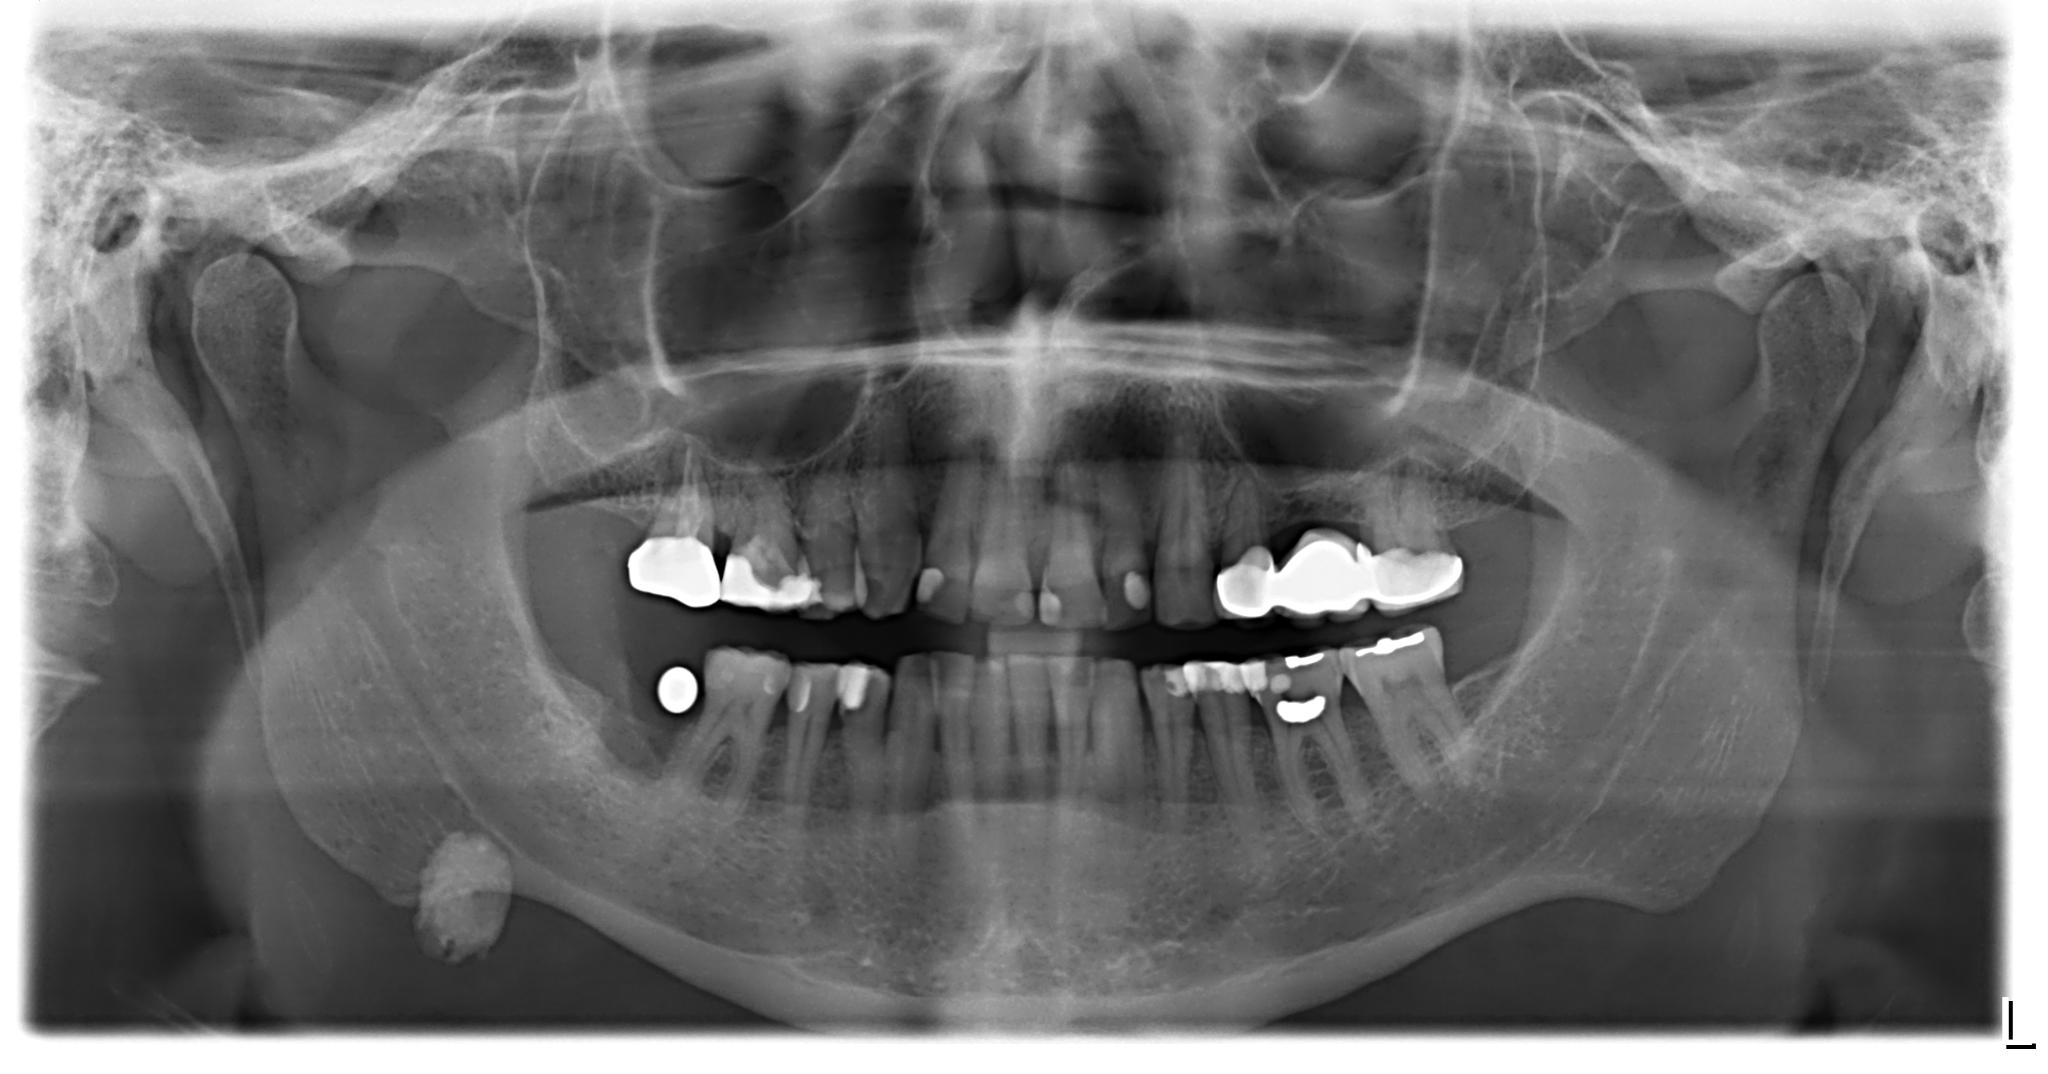

• mit Freilegung

• mit Auswechseln der SekundĂ€rteile

• Knochenaufbau: 1x Regio 47

• Computertomografie

• Funktionsanalyse

Der Zahn wurde im Mai gezogen.